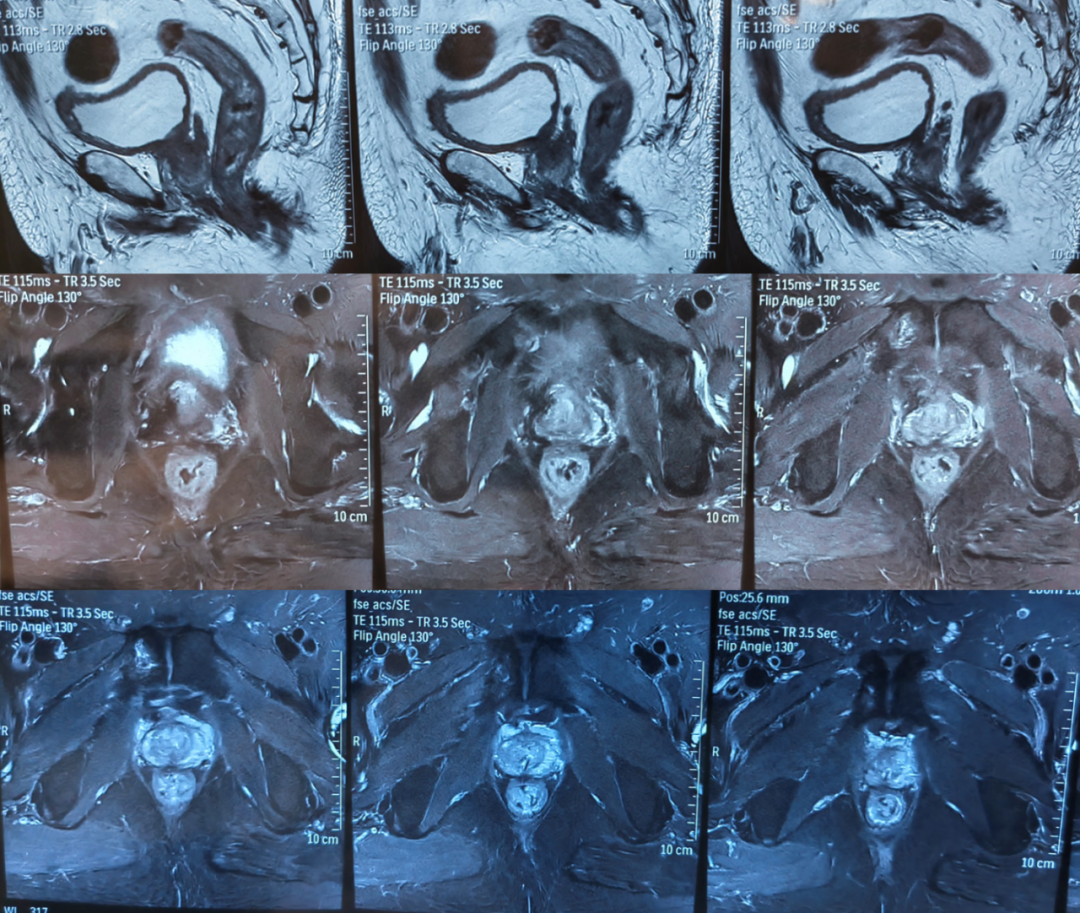

前列腺MR(图1,2024-04-18):1、考虑前列腺癌,PI-RADS 5,膀胱后壁、双侧精囊腺浸润;2、双侧耻骨及第1骶骨异常信号,转移瘤可能。

图1.前列腺MR(2024-04-18):前列腺体积不规则增大,约6.2cm(左右)x5.4cm(前后)x7.1cm(上下),中央带、外周带可见不规则片状短T2等T1信号灶,病灶向上突向膀胱,与膀胱后壁及精囊腺分界不清,DWI示病变呈弥散受限高信号,相应ADC信号减低。盆腔内见多个小淋巴结,较大者短径约为0.6cm。双侧耻骨及第1骶骨见稍长T1长T2信号,DWI弥散受限改变。直肠右侧壁局部增厚。诊断:1、考虑前列腺癌,PI-RADS 5,膀胱后壁、双侧精囊腺浸润;2、双侧耻骨及第1骶骨异常信号,转移瘤可能